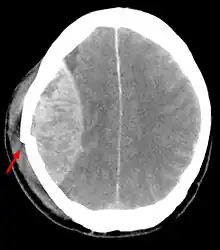

![]() TAC mostrando contusiones cerebrales, hemorragia intracraneal entre los hemisferios, hematoma subdural y fracturas craneales[1] | ||

Las contusiones se encuentran en 20% al 25% de los pacientes con TCE grave. Son lesiones heterogéneas compuestas de zonas de hemorragia puntiforme, edema y necrosis que aparecen en las imágenes de TC como áreas de hiperdensidad puntiforme (hemorragias), con hipodensidad circundante (edema), suelen estar localizadas en la cara inferior del lóbulo frontal y la cara anterior del lóbulo temporal por su relación con el ala mayor del esfenoides. También se pueden encontrar en la superficie de impacto y en la superficie contraria a este, el llamado efecto golpe-contragolpe. Cuando estas evolucionan se parecen más a los hematomas intracerebrales y su ubicación depende el posible efecto de masa.